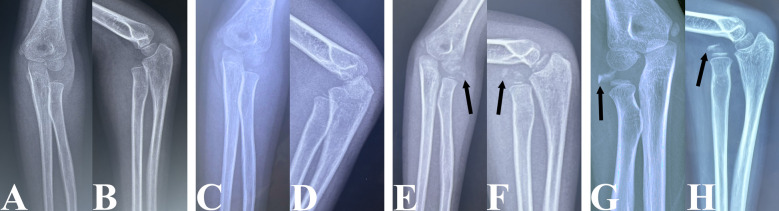

Materials and methods: We retrospectively reviewed 274 patients (mean age at injury: 5.82 ± 2.62 years) with UCMFs with all types of anterior (group A) and non-anterior (group B) radial head (RH) dislocations. Radiographs were used to assess the presence, size and bone density of HO. The risk factors evaluated included age at injury, sex, laterality, interval from injury to diagnosis, presence of radial or median nerve injury, immobilization of the fractured ulna after injury, direction of RH dislocation and distance of RH dislocation (DD-RH). The results were compared with 76 patient demographics-matched paediatric acute Monteggia fractures (PAMFs) undergoing surgery within 48 h after injury.

Results: The HO rate (13.1%) in children with UCMFs was significantly higher than that (0%) in children with PAMFs (P = 0.001). The incidence of HO (14.5%) in group A was significantly higher than that (0%) in group B (P = 0.032). Age at injury and DD-RH were confirmed as risk factors for HO in patients with UCMFs by both univariate and logistic regression analyses (P < 0.05). Receiver operating characteristic curve analysis and chi-squared analysis indicated that age at injury > 6.78 years and DD-RH < 1.59-fold of the narrowest radial neck width were the cut-off values for an increased HO rate in patients with UCMFs (P < 0.05). Increased age at injury (P = 0.041) and interval from injury to diagnosis (P = 0.006) were associated with high-bone density HO.

Conclusions: Patients with UCMFs with anterior RH dislocations, age at injury > 6.78 years, and DD-RH < 1.59-fold of the narrowest radial neck width were more likely to develop HO. The bone density of HO increases with age at injury and interval from injury to diagnosis. Timely RH reduction after acute injury may prevent HO.